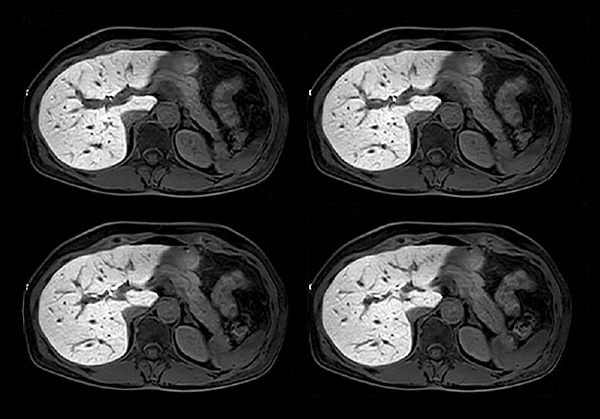

Patient with multiple liver lesions showing up hyperintense on T2-weighted images. The high spatial resolution of MultiVane XD can be appreciated by comparing the images demonstrating the two hyperintense focal liver lesions. mDIXON Quant was performed for quantification of intralesional and hepatic parenchymal fat content. The fat content in the liver parenchyma was normal. The lesion has a fat fraction of 25-30%. Histopathologic diagnosis was hepatocellular adenoma.